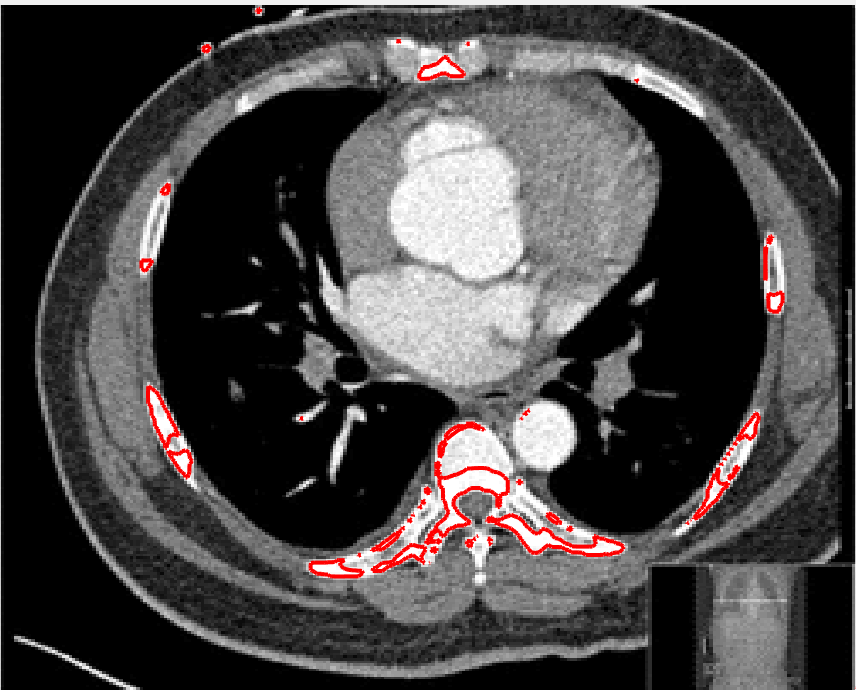

Four sets of test results are shown below. In Test 1 we compare models M1 – M6 to the proposed model M7 for two images which are hard to segment. The first is a CT scan from which we would like to segment the lower portion of the heart, the second is an MRI scan of a knee and we would like to segment the top of the Tibia. See Figure 9 for the test images and the marker sets used in the experiments. In Test 2 we will review the sensitivity of the proposed model to the main parameters. In Test 3 we will give several results achieved by the model using marker and anti-marker sets. In Test 4 we show the initialisation independence and marker independence of the Geodesic Model on real images.

In this test we give the segmentation results for models M1 – M7 for the two challenging test images shown in Figure 9. The marker and anti-marker sets used in the experiments are also shown in this figure. After extensive parameter tuning, the best final segmentation results for each of the models are shown in Figures 10 and 11. For M1 – M4 we obtain incorrect segmentations in both cases. In particular, the results of M2 and M4 are interesting as the former gives poor results for both images, and the latter gives a reasonable result for Test Image 1 and a poor result for Test Image 2. In the case of M2, the regularisation term includes the edge detector and the distance penalty term (see (4)). It is precisely this which permits the poor result in Figures 10(b) and 11(b) as the edge detector is zero along the contour and the fitting terms are satisfied there (both intensity and area constraints) – the distance term is not large enough to counteract the effect of these. In the case of M4, the distance term and edge detector are separated from the regulariser and are used to weight the Chan-Vese fitting terms (see (9)). The poor segmentation in Figure 11(b) is due to the Chan-Vese terms encouraging segmentation of bright objects (in this case), weighting enforces these terms at all edges in the image and near . In experiments, we find that M4 performs well when the object to segment is of approximately the highest or lowest intensity in the image, however when this is not the case, results tend to be poor. We see that, in both cases, models M5 and M6 give much improved results to M2 and M4 (obtained by incorporating the geodesic distance penalty into each). The proposed Geodesic Model M7 gives an accurate segmentation in both cases. It remains to compare M5, M6 and M7. We see that M5 is a non-convex model (and cannot be made convex [39]), therefore results are initialisation dependent. It also requires one more parameter than M6 and M7, and an accurate set to give a reasonable area constraint in (4). These limitations lead us to conclude M6 and M7 are better choices than M5. In the case of M6, it has the same number of parameters as M7 and gives good results. M6 can be viewed as the model M7 with weighted intensity fitting terms (compare (18) and (30)). Experimentally, we find that the same quality of segmentation result can be achieved with both models generally, however M6 is more parameter sensitive than M7. This can be seen in the parameter map in Figure 12 with M7 giving an accurate result for a wider range of parameters than M6. To show the improvement of M7 over previous models, we also give an image in Figure 13 which can be accurately segmented with M7 but the correct result is never achieved with M6 (or M3). Therefore we find that M7 outperforms all other models tested M1 – M6.

Test 3 – Further Results from the Geodesic Model M7. In this test we give some medical segmentation results obtained using the Geodesic Model M7. The results are shown in Figure 14. In the final two columns we use anti-markers to demonstrate how to overcome blurred edges and low contrast edges in an image. These are challenging and it is pleasing to see the correctly segmented results.

(i) (ii) (iii) (iv) (v)